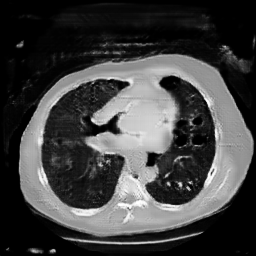

The study utilizes three 3D datasets, namely the GSP dataset[3], the LIDC-IDRI dataset[1], and the dataset employed for the Lung Nodule Analysis 2016 (LUNA16) challenge[21] which is a subset of LIDC-IDRI dataset. Samples from generated images at different stages of training are presented in Fig. 2 and Fig.3.

Refer to caption

20000

30000

40000

50000

60000

70000

80000

HA-GAN synthetic images at different iterations

Figure 3: Synthetic images of CRF-GAN and HA-GAN at different iterations of training on the LUNA16 dataset